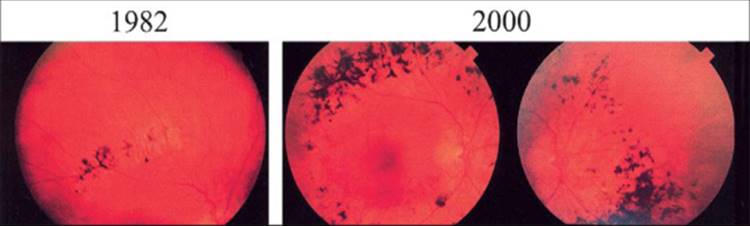

Other atypical forms of RP include pericentral, paravenous, or unilateral RP. The pericentral form is characterized by a near mid-peripheral scotoma extending from the 5-30° isopter (Fig. 177.17) (in contrast to typical RP where the field loss initially extends from the 20-40° isopter), single flash (0.5Hz) ERGs greater than 100 ?V and 30-Hz cone ERGs greater than 15 ?V initially (Fig. 177.18), and a normal or nearly normal fial dark adaptation threshold in the periphery. This form progresses at a slower rate than typical RP; in later life they can lose central vision but they retain considerable peripheral vision.[153]The paravenous form is usually characterized by slightly reduced full-field ERGs and intraretinal pigment and atrophy of the pigment epithelium confied to the distribution of the retinal veins in each eye. In some cases the macula degenerates as well (Fig. 177.19). Patients with paravenous disease may lose central vision but, like pericentral RP, they retain peripheral vision into later life.[154] Unilateral RP is characterized by fundus changes of RP in one eye with no evidence of RP in the fellow eye. Full-field ERGs are substantially reduced in the affected eye and normal in the fellow eye. Patients with unilateral RP have progressive disease in the affected eye but have not been observed to develop a generalized form of RP in the fellow eye at a later time. Pericentral RP can be inherited by a recessive or dominant mode while paravenous and unilateral RP have been found characteristically in patients with no family history of this condition. No evidence exists that patients with pericentral, paravenous, or unilateral RP will benefit from vitamin A treatment.

FIGURE 177.17 Fundus photographs for a patient with pericentral retinitis pigmentosa to show an increase in pericentral bone-spicule pigmentation over an 18-year interval.

Reprinted from Am J Ophthalmol, vol 140, Sandberg MA, Gaudio AR, Berson EL. Disease course of patients with pericentral retinitis pigmentosa, pp 100-106, Copyright 2005 from Elsevier Science.